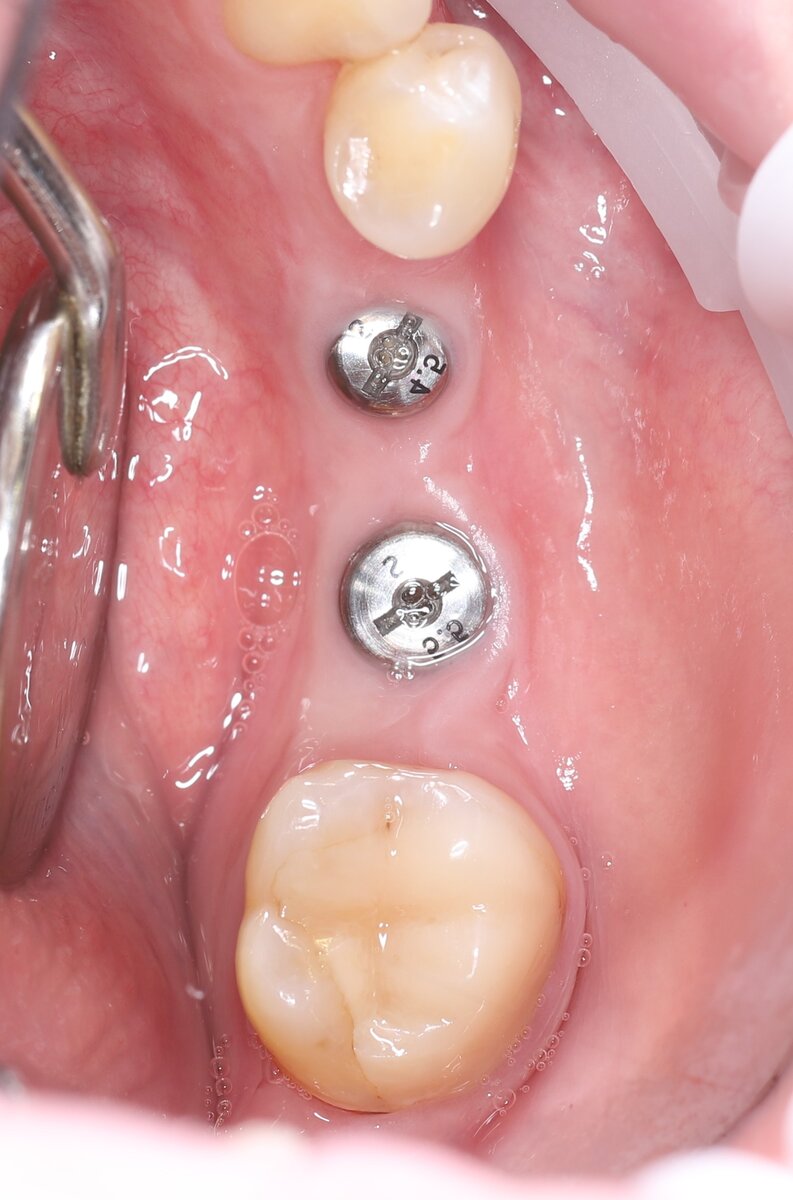

Посмотрите внимательно на это фото. Установлены имплантаты, в них закручены формирователи десны:

Здесь я установил 2 имплантата, но прикреплённой десны мало. ~ 1 мм с щёчной стороны:

И чтобы минимизировать в будущем риск заброса пищи в пространство между коронкой и имплантатом, нужно создать хороший объём неподвижной слизистой. Это будет своего рода барьер, не дающий проникать пищевым остаткам внутрь.